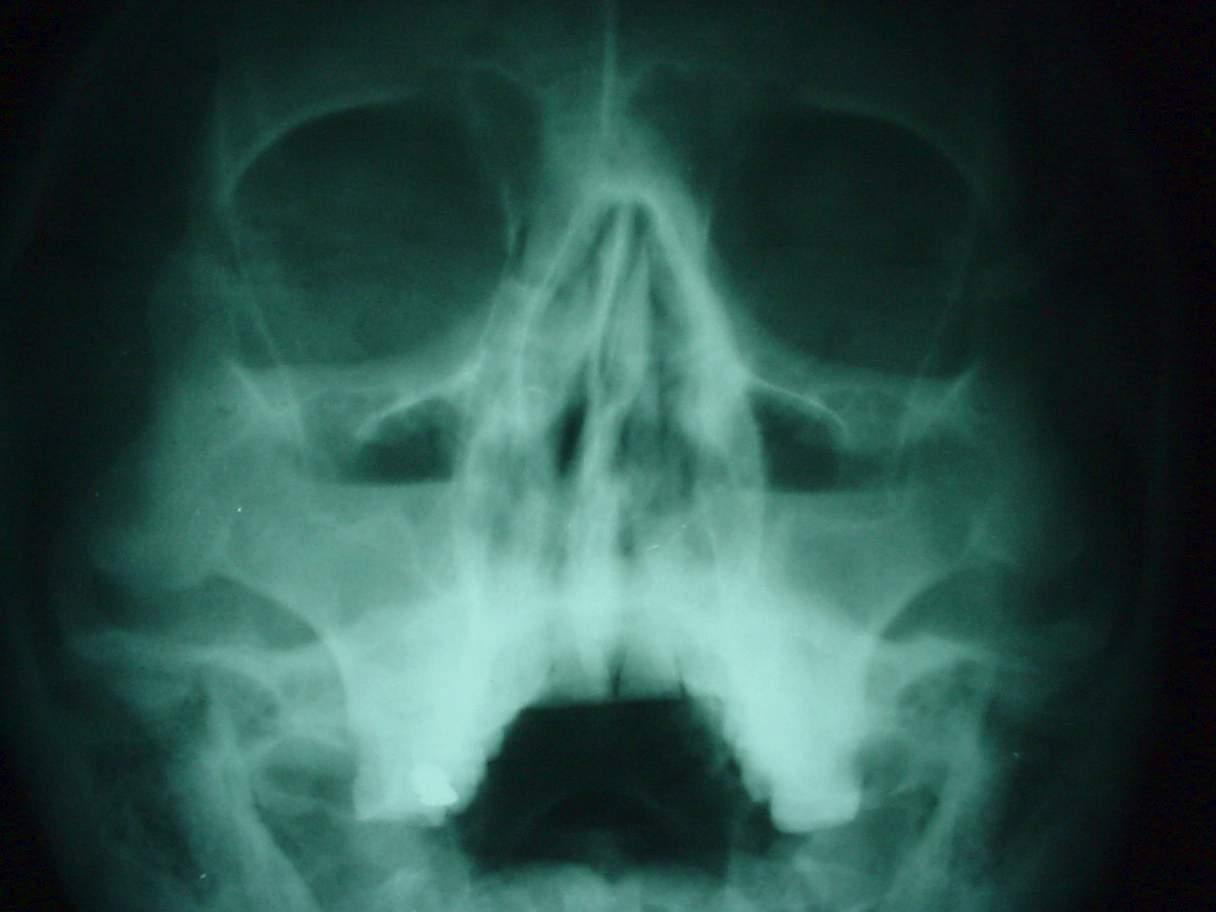

Nose and PNS Clinical Photos for Static Stations